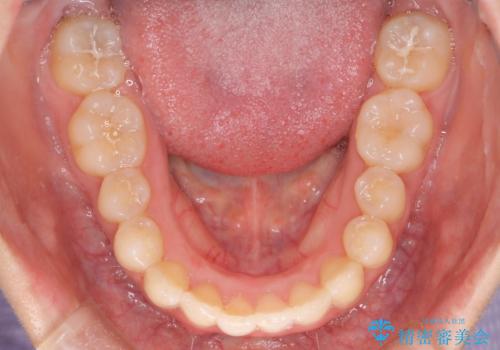

強い叢生がありましたが、抜歯は行わず上下顎ともに、主に歯列弓の拡大とディスキング(歯と歯の間に隙間を作る処置)を行い叢生を改善しました。

見た目、嚙み合わせ及び、治療期間や施術内容に大変ご満足いただきました。